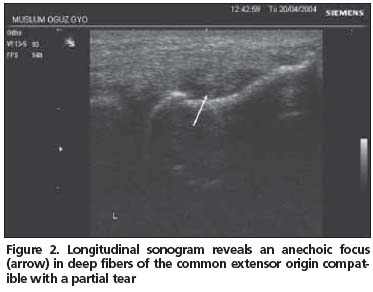

Tendon echotexture was accepted to be normal if a uniform fibrillar pattern could be traced between the muscle and the attachment to the lateral condyle. Tendinopathy was described if there was a loss of this normal fibrillar pattern that is seen as focal areas of hypoechogenicity. A partial tear was defined as a focal anechoic area with no fibers intact or an echogenic irregular band that could run either horizontally or longitudinally in the common extensor origin. A complete tear was defined as a distinct complete interval traversing or extending through the full width of the common extensor origin. Confirmation of the abnormality was performed by imaging at least the two planes. Enthesopathy was diagnosed if the proximal part of the common extensor origin was enlarged and there were echogenicity alterations. Focal areas of calcification and thickening of the peritendinous lining (peritendinitis) were recorded, and bursitis on the inferior surface of the extensor carpi radialis brevis tendon was noted[1,4,16].

Fifty-two patients (39 women, 13 men; mean age: 47.5 years [SD 9.6]) with LE participated in this study. US examinations in 24 (46.2%) patients were normal (Group 1). Initial clinical diagnosis of LE was confirmed by US in 28 (53.8%) patients (Group 2). US pathologic findings were: tendinopathy (n: 25, 89.2%), partial tear (n: 5, 17.9%), enthesopathy (n: 4, 14.3%), focal areas of calcification (n: 5, 17.9%), peritendinitis (n: 3, 10.7%), and bursitis (n: 3, 10.7%) in Group 2 patients (Figures 1,2, 3). Three patients had partial tear or enthesopathy or peritendinitis alone without tendinopathy. All of the bursitis was accompanied with a partial tear. We did not detect a complete tear of the common extensor origin.